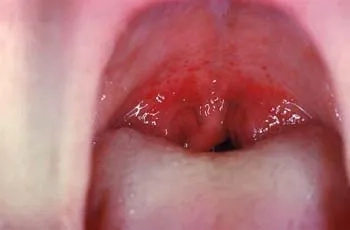

Image description of adenovirus infection

Adenovirus Infection is a viral illness affecting the respiratory and gastrointestinal systems. It spreads easily through contact and causes fever, cough, and digestive issues.